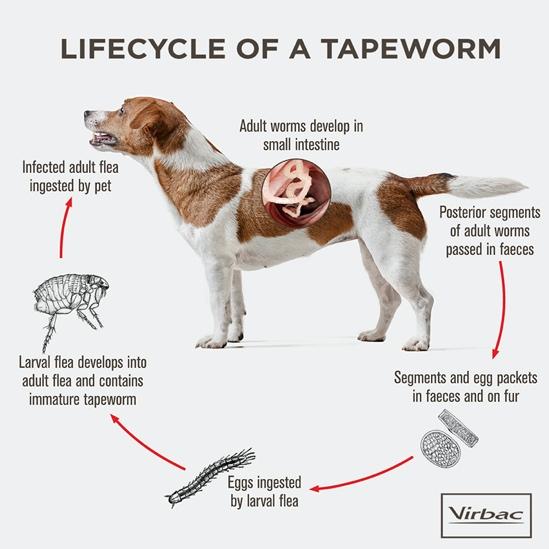

Deworming and parasite control involves treating pets for internal and external parasites such as roundworms, tapeworms,...